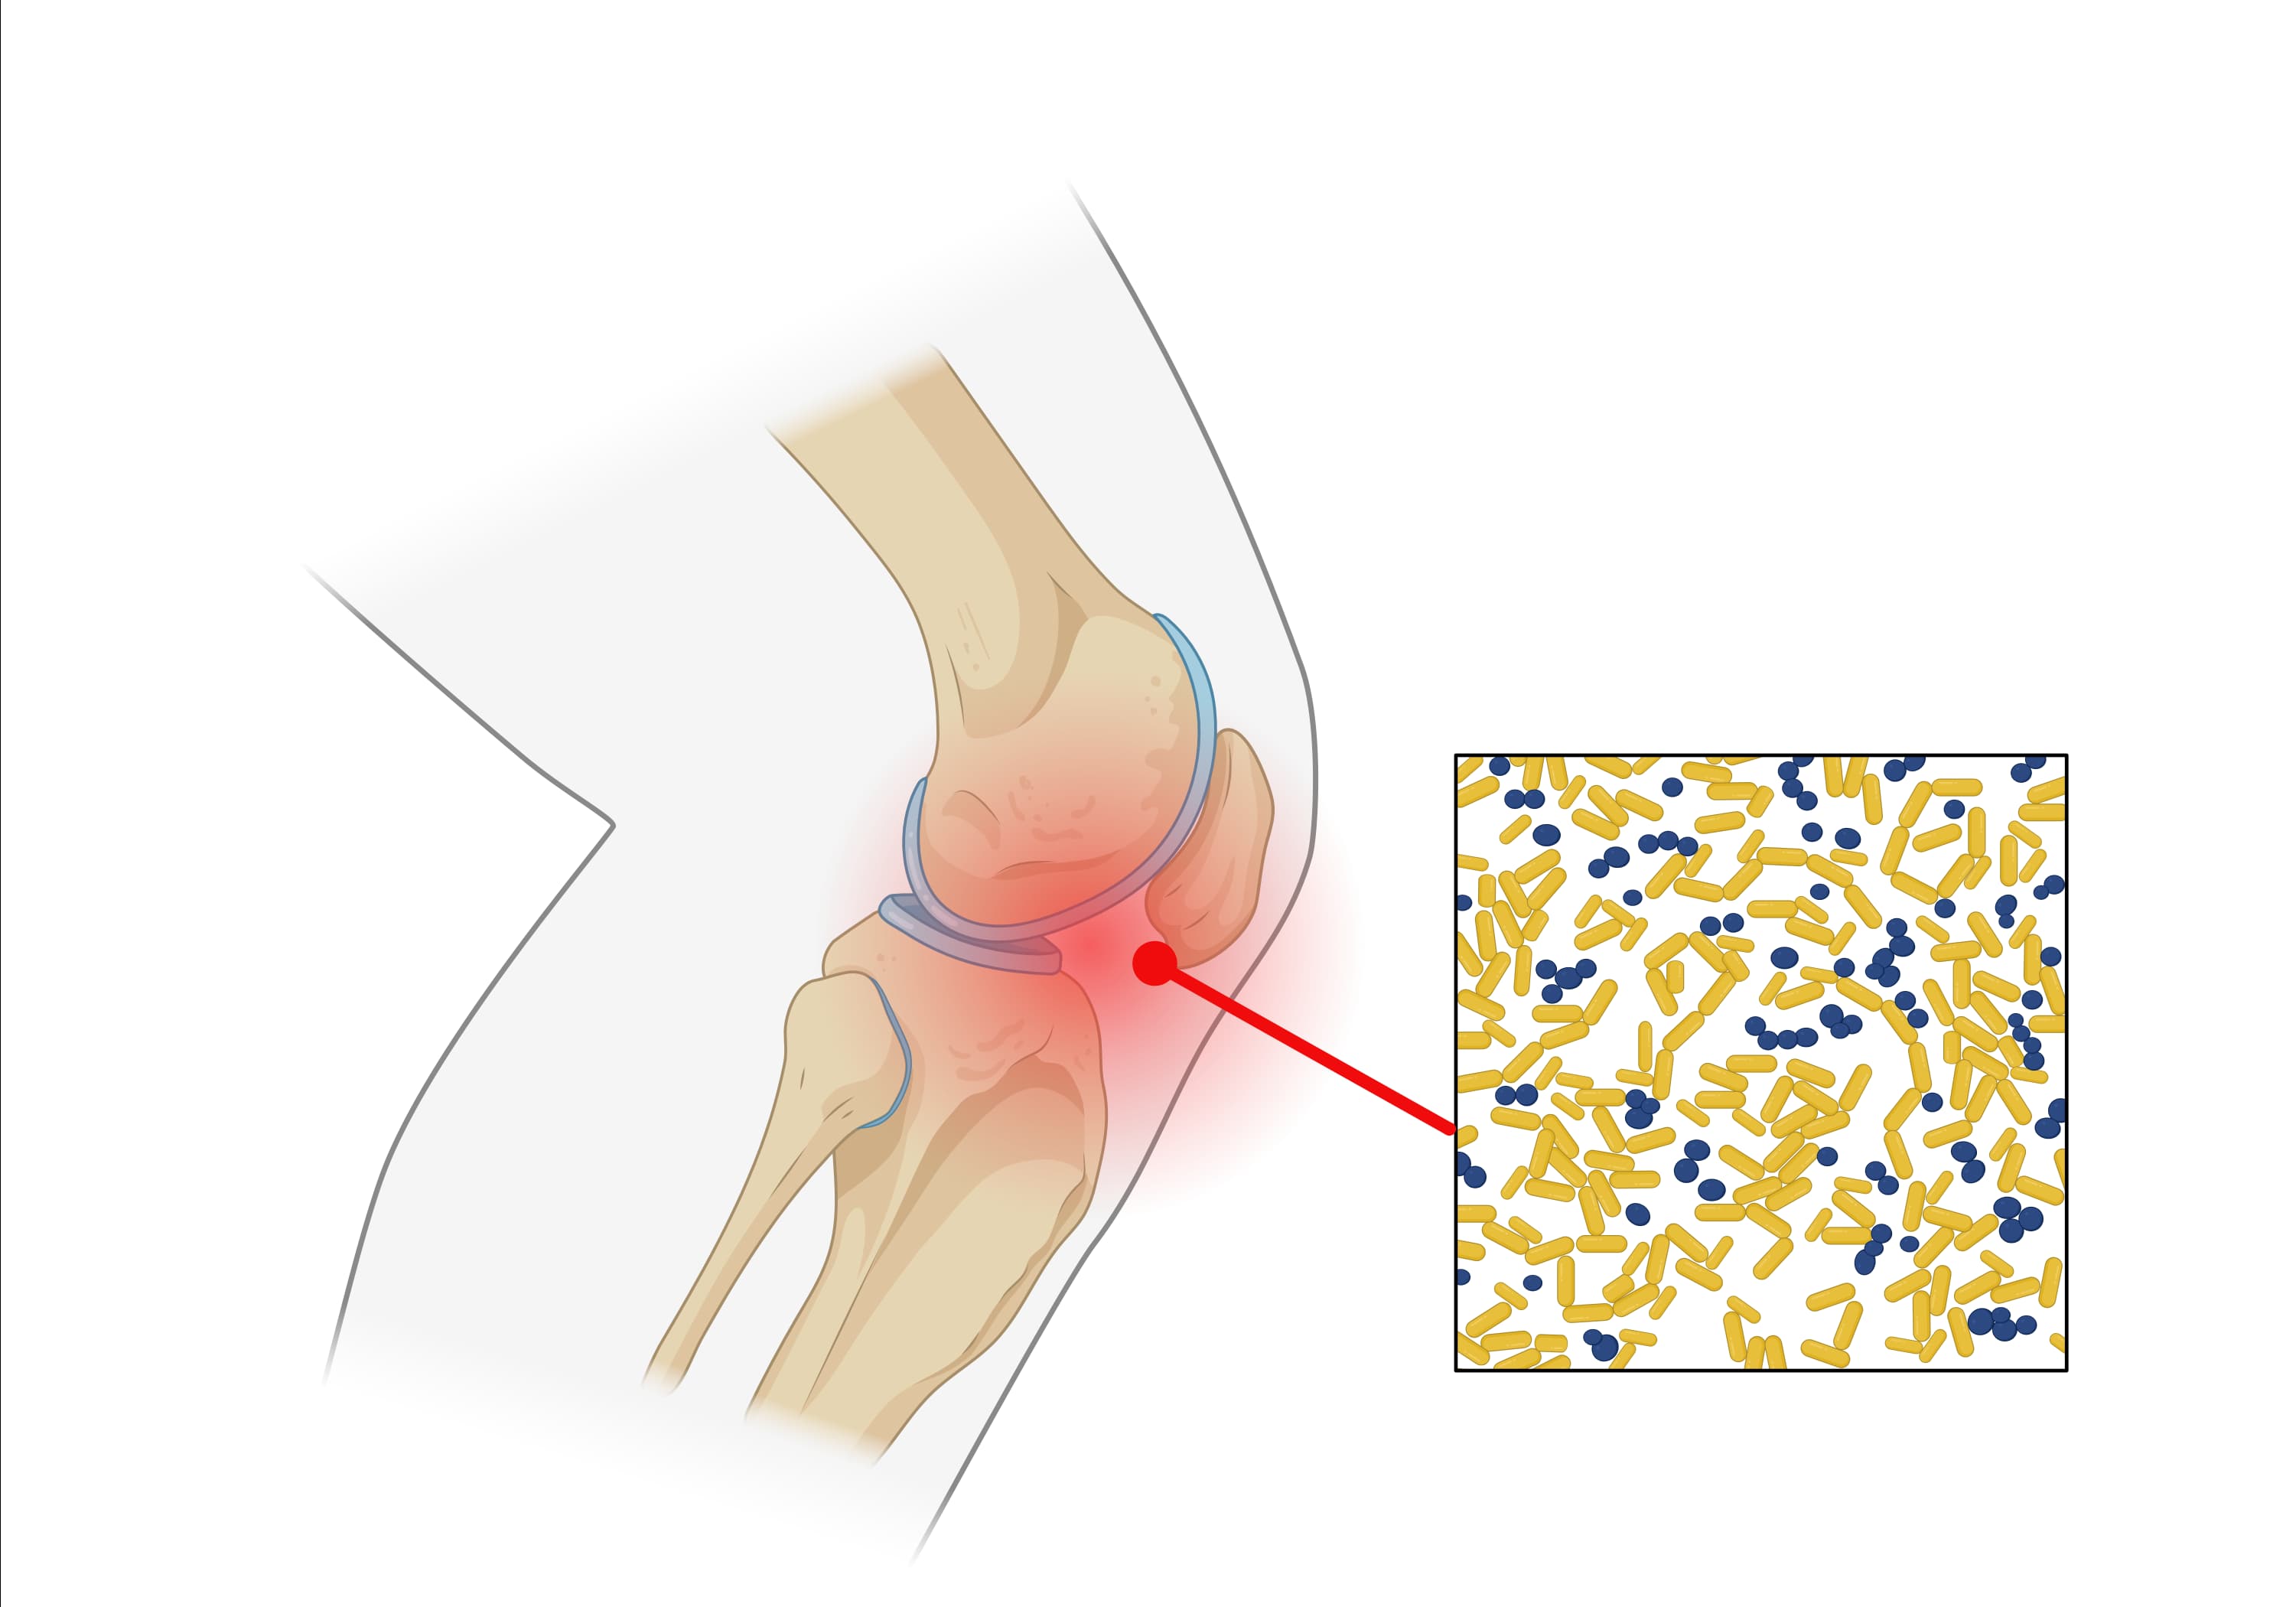

Septic arthritis

Prediction of septic arthritis.

Explore our collection of statistical models designed to predict the probability of septic hip arthritis or septic knee arthritis.